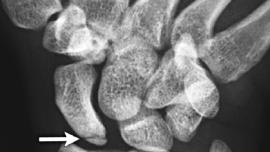

Artificial intelligence improves wrist fracture detection

Missed fractures are a common category of diagnostic errors and can cause malunion, osteonecrosis, and arthritis, with consequent

10 November 2018, 18:00 PM